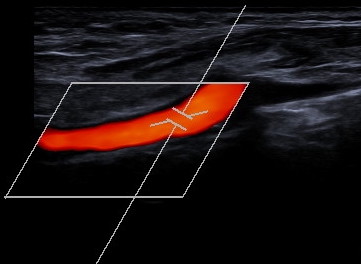

Gefäßdarstellung mittels Ultraschall

Bei der Doppler-Duplex-Sonographie der Halsgefäße wird untersucht, ob Verkalkungen (Plaques) vorliegen, und ob es dadurch zu Verengungen (Stenosen) kommt.

Neben dem Aussehen der Plaques wird die lokale Flussgeschwindigkeit des Blutes beurteilt: Je schneller die Flussgeschwindigkeit, desto hochgradiger die Stenose.